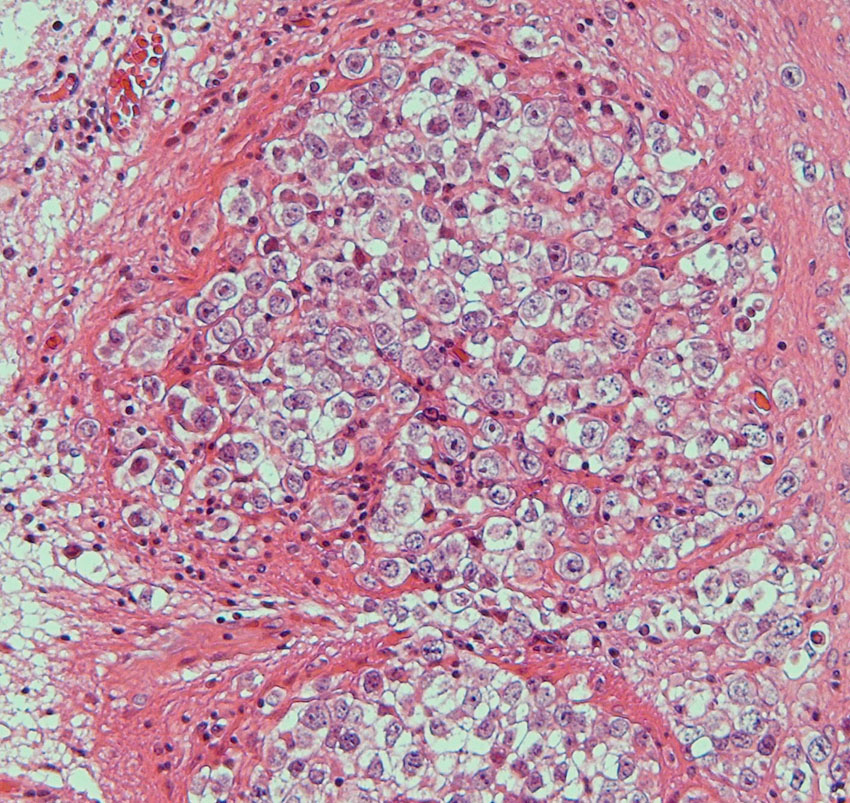

病理所見です

epidermisにhair follicle, sebaseous glandを伴うdermoid cyst 類皮のう胞の診断です。上皮に接する脳組織(これは正常脳組織ではなくて成熟奇形腫の内部にできた脳組織)の内部にgerm cell nest(矢印)が認められました(左下拡大)。mature teratomaにgerminomaが混在するmixed germ cell tumor と診断されました。